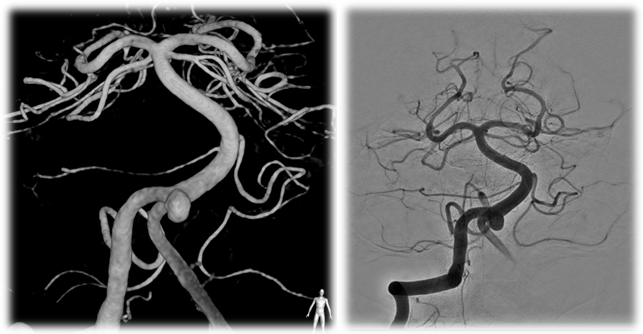

Date Posted: Saturday, August 01, 2015On June 30, 2015, Dr. Ajit S. Puri became the first physician in the United States to use the Atlas Stent for cerebral aneurysm stent-assisted coiling treatment for one of our neurointerventional patients. Endovascular treatment of cerebral aneurysms is a minimally invasive technique that has evolved rapidly since the first detachable coils were used to treat a patient in 1991. The procedure involves accessing the brain’s blood vessels with tiny plastic catheters introduced through a small puncture in the groin. The embolization coils used to treat the aneurysm are made of a metal that has a memory so that when the coils are advanced into the aneurysm, the metal unfolds, filling the space within the aneurysm. Advanced techniques in endovascular therapy have evolved to allow for the use of stents, similar in concept to the types of devices used to treat coronary artery disease, as an adjunctive therapy to treat wide-neck aneurysms. The stents serve as scaffolding for coil placement and prevent intrusion into the “parent” artery while allowing for the maximum number of coils to be deployed within the aneurysm.

![]() Figure 1-Pretreatment images of the aneurysm |